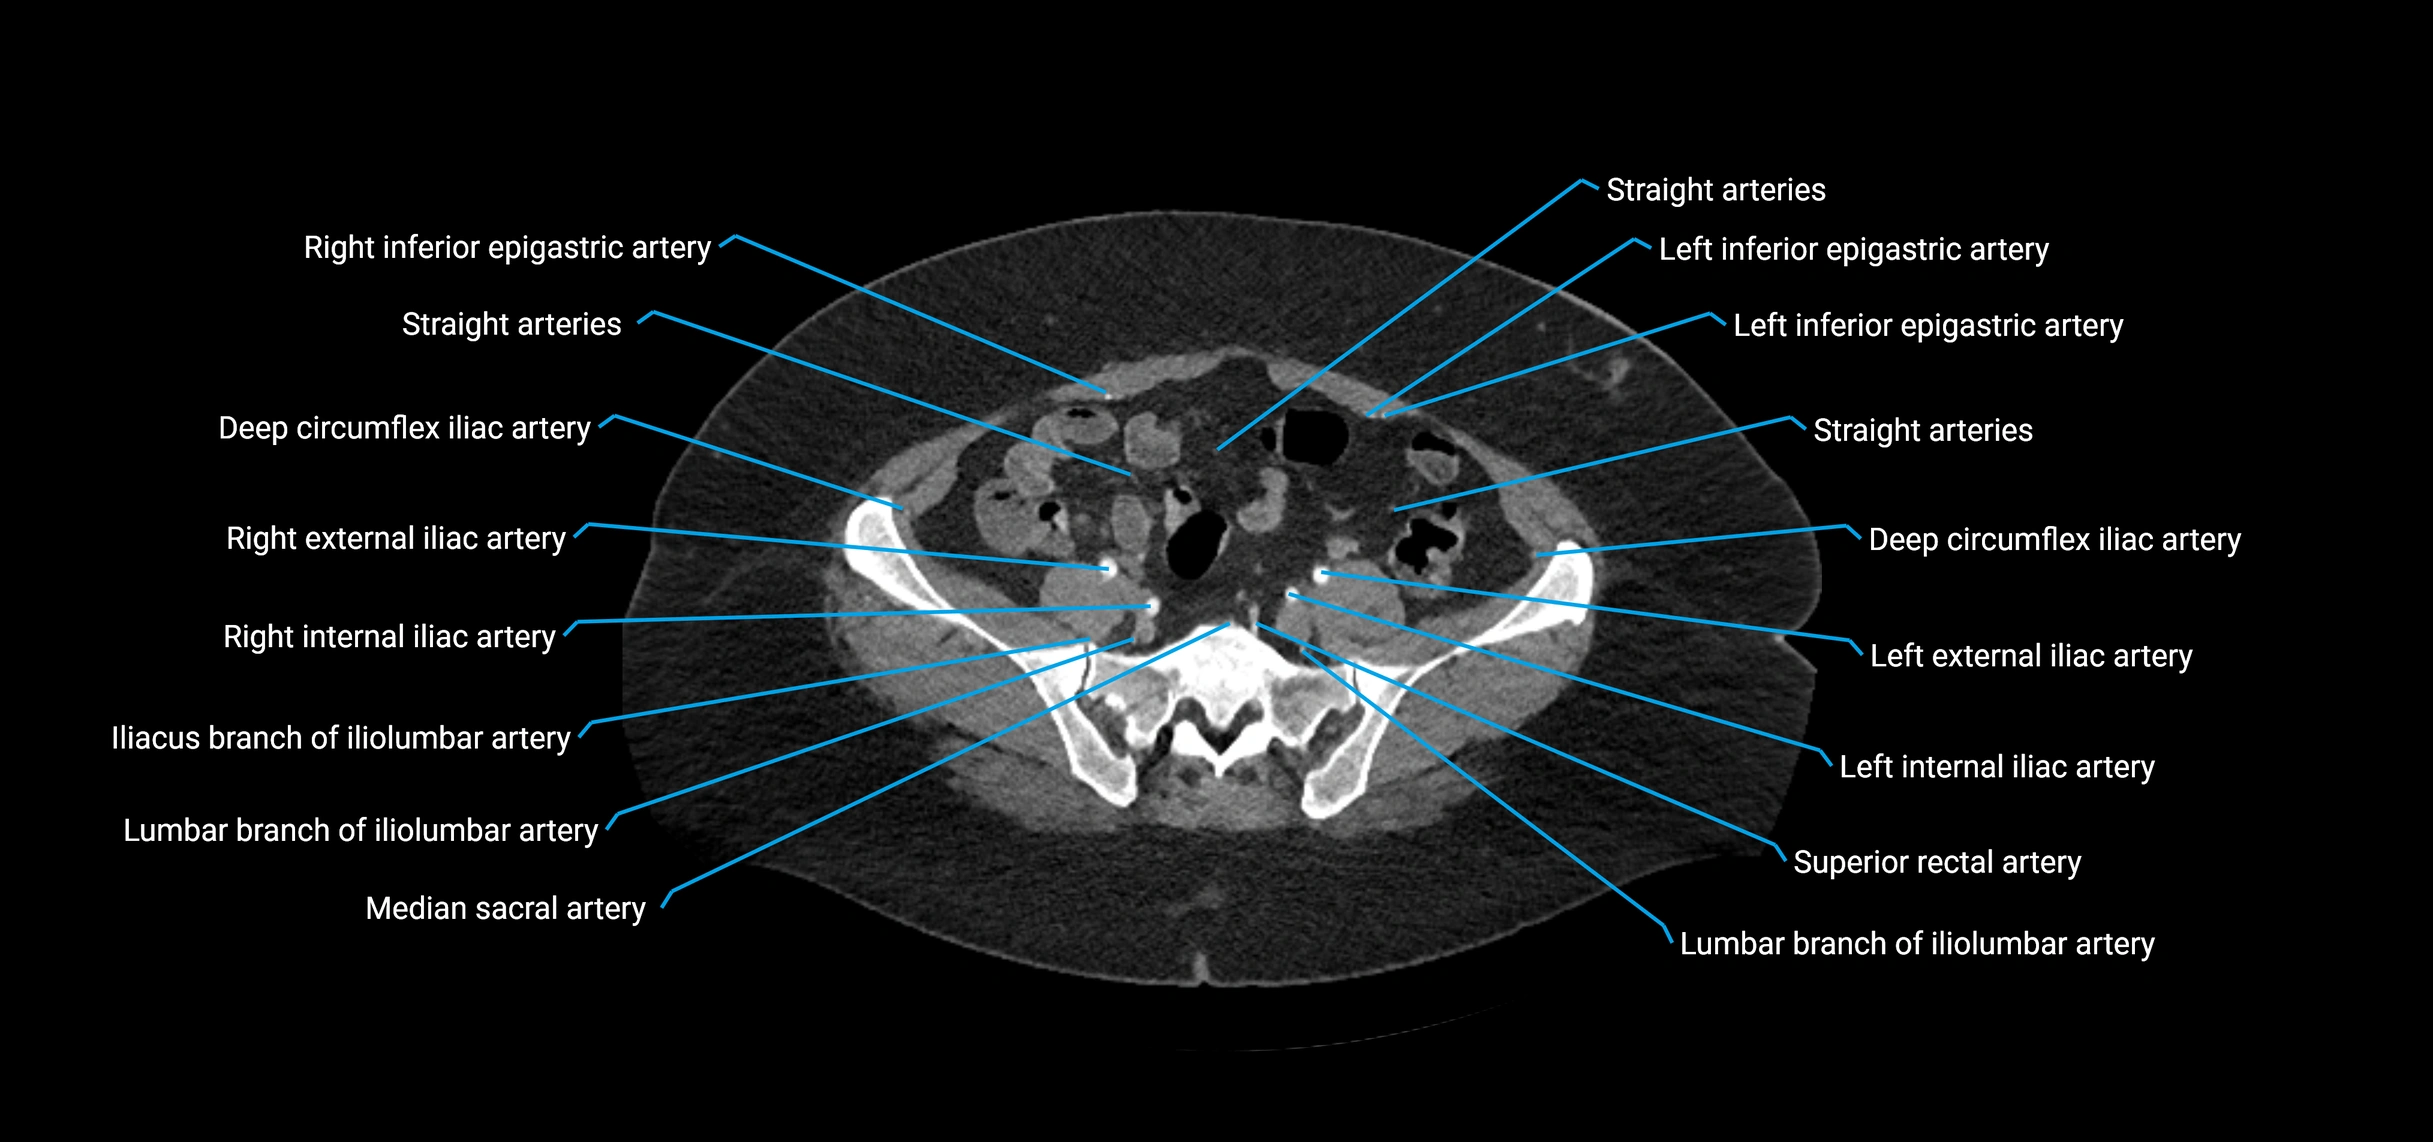

Contrast-enhanced CT (CTA):

• Gold standard for abdominal aortic imaging

• Provides excellent detail of lumen, wall, aneurysm, thrombus, and branch vessels

• Multiplanar and 3D reconstructions help in aneurysm measurement, stent graft planning, and dissection evaluation

• Detects acute rupture, traumatic injury, or occlusion with high sensitivity